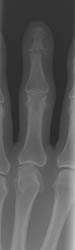

Early findings include soft tissue swelling and effusions. With progression

of the infectious process, destruction of articular cartilage and bone can

lead to radiographic findings of poorly defined articular erosions and joint

space narrowing. Juxtaarticular osteoporosis and central erosions can also

be noted and ankylosis of the joint may eventually result in the most severe

cases.